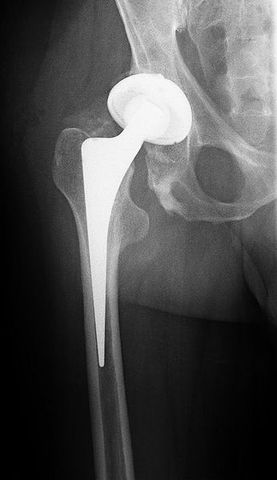

Una protesis de titanio, con una cabeza ceramica y copa acetabular de polietileno. El reemplazo total de cadera, conocido en términos médicos como artroplastia de cadera, consiste en la cirugía ortopédica que busca reemplazar de forma total o parcial la articulación de la cadera con un implante artificial llamado prótesis.